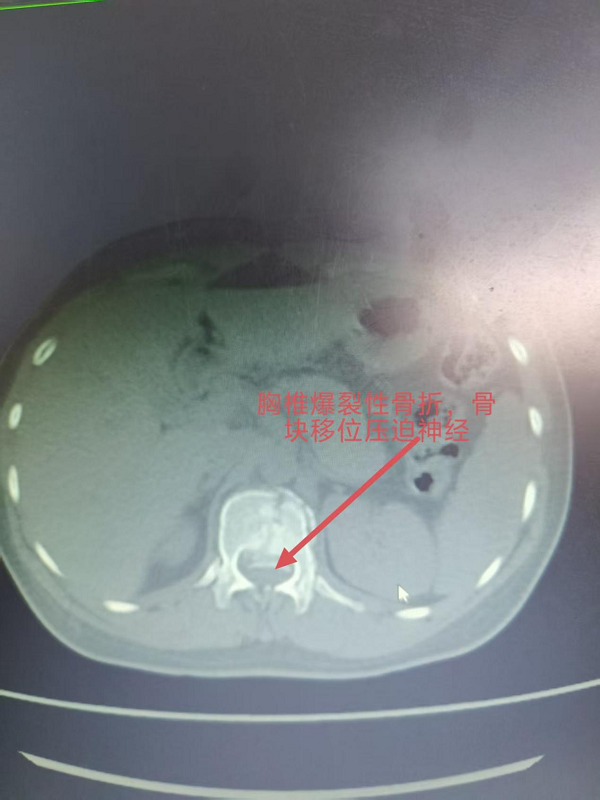

3. 为胸椎爆裂性骨折患者施后路切开复位、微创减压内固定术(四级手术),胸椎爆裂性骨折常因高能量损伤导致,骨折块可能突入椎管压迫脊髓,致残风险高。丁晔副主任医师团队采用微创理念进行减压,并完成了有效的复位与坚强的内固定,既解除了对神经的压迫,又最大程度地减少了手术创伤,为患者争取了最佳的神经功能恢复条件。